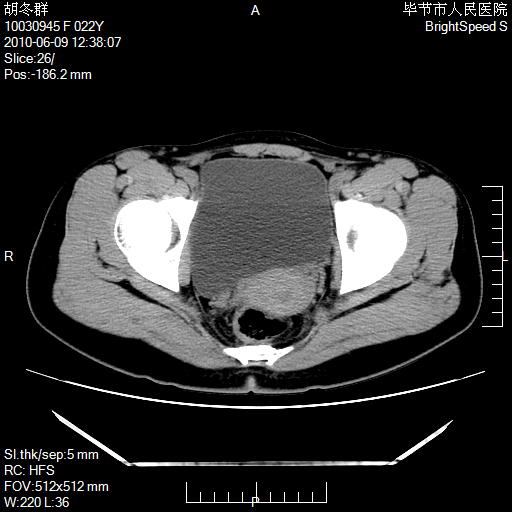

患者23岁,发现腹部包块3月。

左侧卵巢囊腺瘤或囊腺癌

盆腔内囊性占位性病变;考虑左侧卵巢囊腺瘤。

有分隔、壁薄,支持考虑左侧卵巢囊腺瘤。

左侧卵巢浆液性囊腺瘤。

有分隔、壁薄,支持考虑左侧卵巢囊腺瘤。排尿后,膀胱缩小,由于重力作用,肿块下移就到了膀胱位置,很好理解。